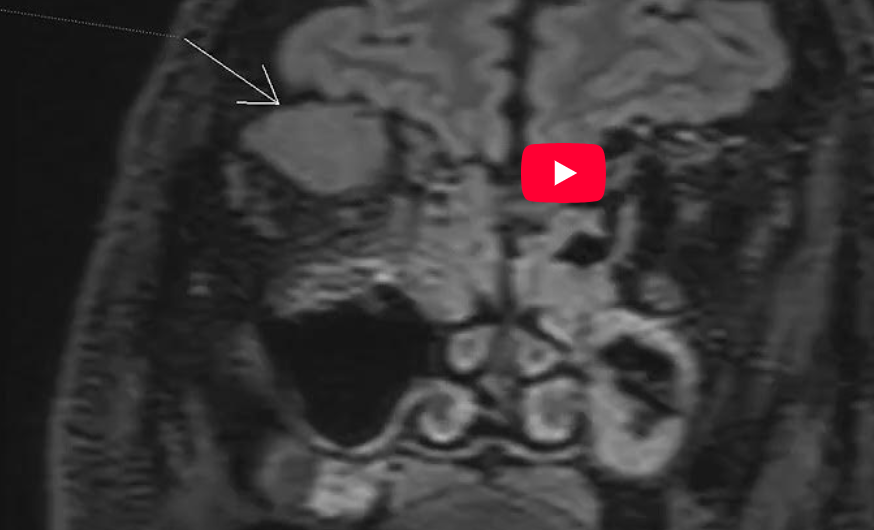

CAZ nr 79: Miozită de muşchi drept superior

Video 2: oblic coronal space T2

Discuţie caz nr 79: Pacienta a efectuat examinare IRM cerebrală și de orbite pentru diagnosticul de exoftalmie. Imaginile evidențiază creștere de volum a mușchiului drept superior la nivelul orbitei drepte.

Miozita orbitară este o afecțiune clinică rară care implică inflamația idiopatică, în principal a mușchilor extraoculari. Diagnosticul miozitei orbitale necesită o examinare detaliată, teste de laborator și scanare IRM ale orbitelor pentru a exclude alte boli. Opțiunea de tratament de primă linie este terapia sistemică cu corticosteroizi cu terapie imunosupresoare suplimentară, dacă este necesar.

DE LUAT ACASĂ!!! Pentru examinarea IRM a orbitelor se folosește un protocol special dedicat cu achiziția T1 pre și postcontrast cu saturația grăsimii; în acest caz se poate observă Video 5 efectuat postcontrast fără saturația grăsimii pentru parenchimul cerebral în comparație cu imaginile coronale T1 cu saturația grăsimii Video 7.